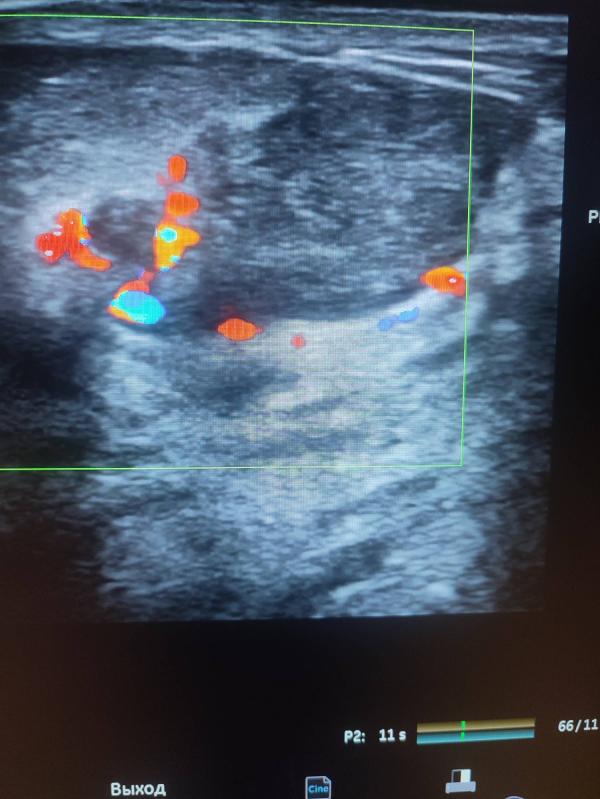

Добрый день девочки ! Хочу рассказать случай из практики: вчера у меня на приеме была девочка , возраст 31 год, планово готовилась на ЭКО, замужем 3 года! При УЗИ молочных желез было выявлено вот такие образования- точнее сказать рак левой молочной железы! В данном случае ни о какой беременности речи быть не может, тем более ЭКО ! Здесь длительное лечение , с последующей долгой реабилитацией! Самое интересное ,что она уплотнения отмечала давно , но к врачу не ходила ! (((